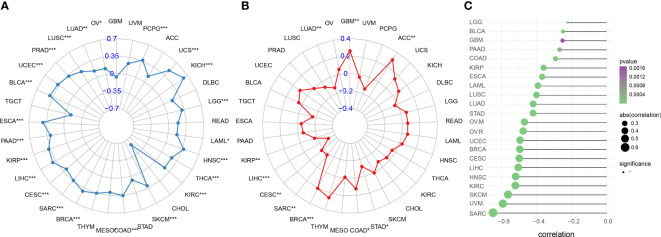

Correlation between IFN-γ score and immunotherapy response markers